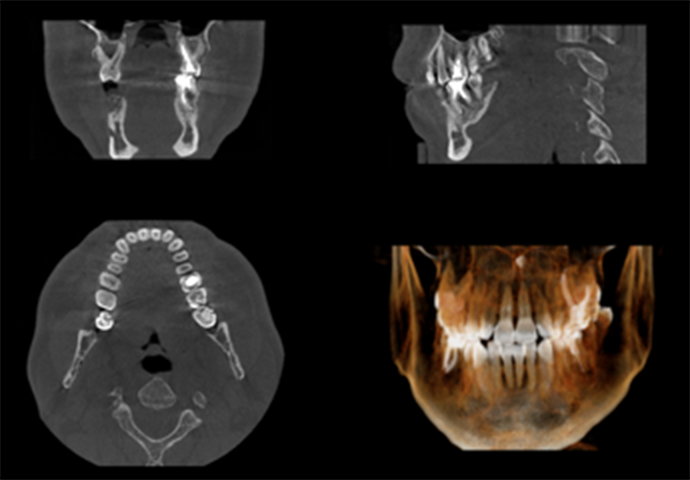

口腔がんには癌腫(舌がん、歯肉がんなど)、肉腫(顎骨の骨肉腫など)、造血器の悪性腫瘍(首や顎骨内の悪性リンパ腫など)といった種類があります。中でも、癌腫の舌がんや歯肉がんは口腔がんの中でも発生する割合が高いとされています。